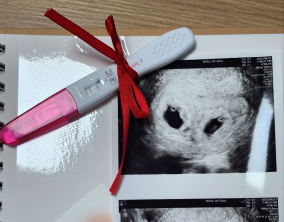

두 줄에서 심장소리까지, 따뜻하게 이어진 시간